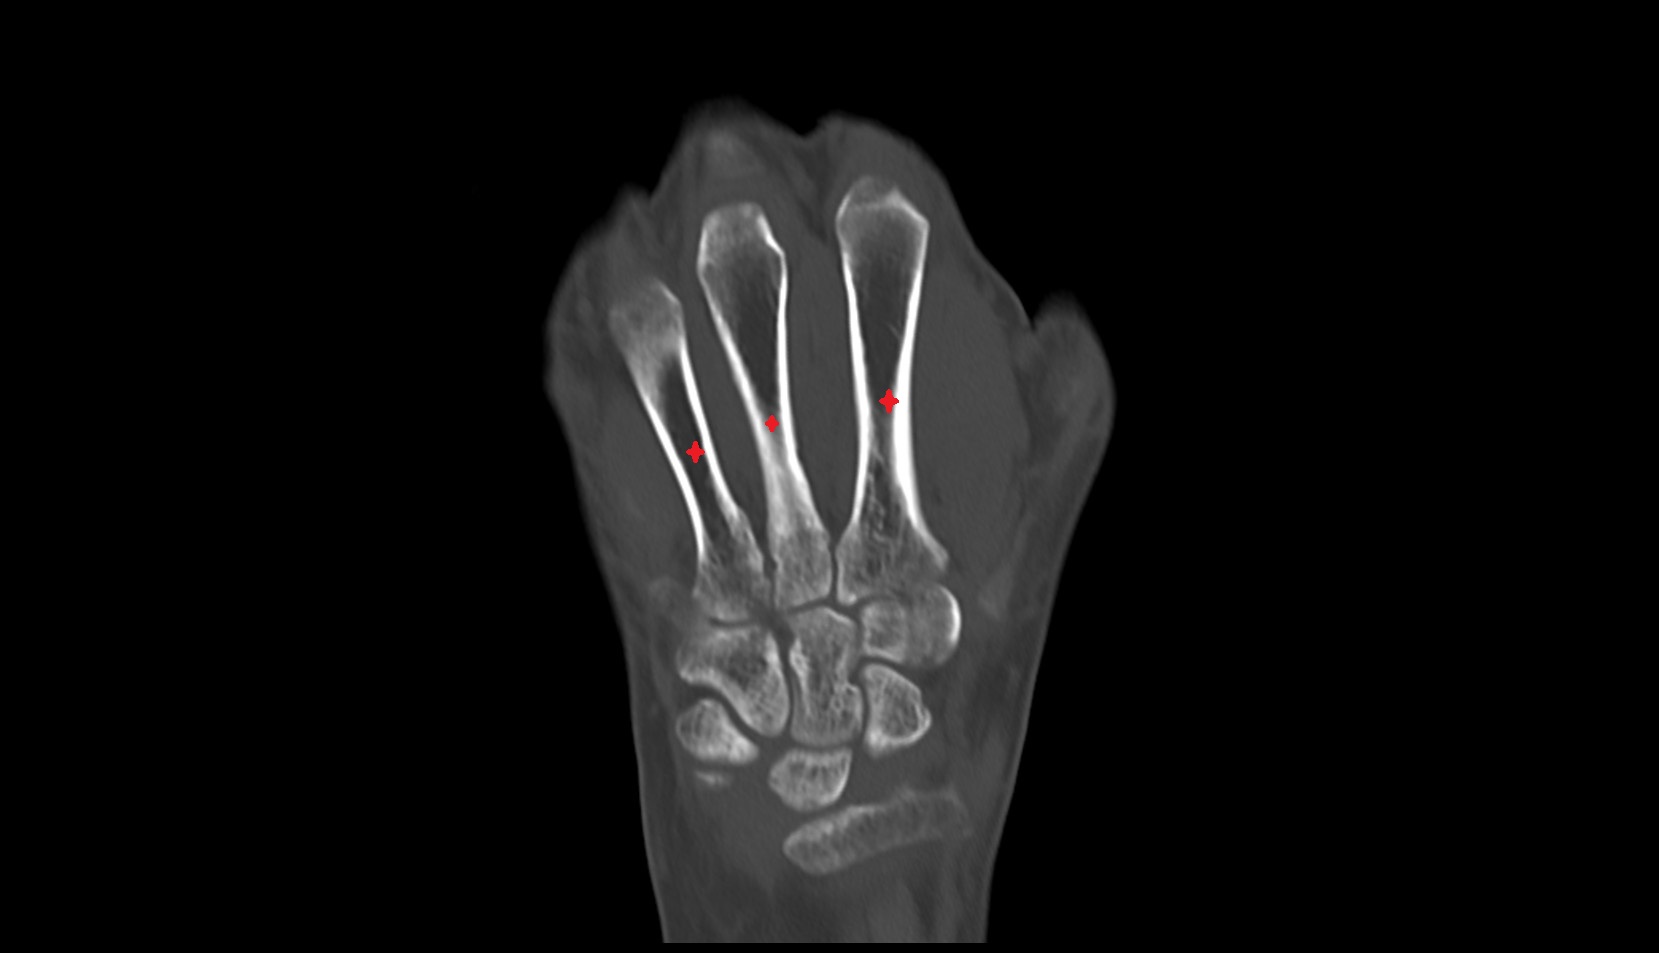

- Cubital tunnel